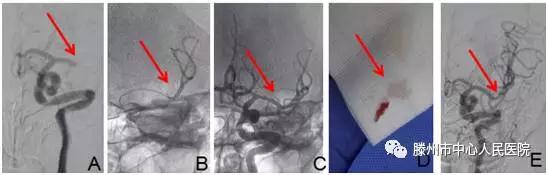

明確診斷為“腦栓塞”后,告知患者家人病情,建議機械取栓治療。患者家人同意后,急診科護士迅速護送病人于9:35分進入介入手術(shù)室。再次與患者溝通病情并積極行手術(shù)準(zhǔn)備。9:40股動脈穿刺成功,造影見左側(cè)大腦中動脈M1段以遠閉塞(圖A),10點10分支架微導(dǎo)管到位(圖B)

10點19分Soltaire-AB支架到位打開后血流恢復(fù)(圖C),患者癥狀明顯減輕,等待5分鐘后,支架取出長條狀血栓(圖D),患者癥狀完全緩解,言語及肢體力量完全恢復(fù)正常。觀察10分鐘病情無反復(fù),再次造影左側(cè)大腦中動脈顯影完全正常(圖E),結(jié)束手術(shù),安返病房。